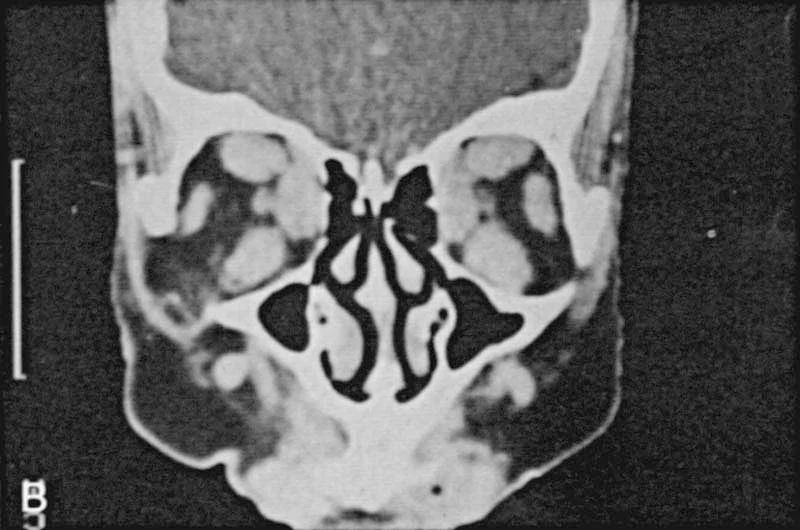

• Orbital decompression